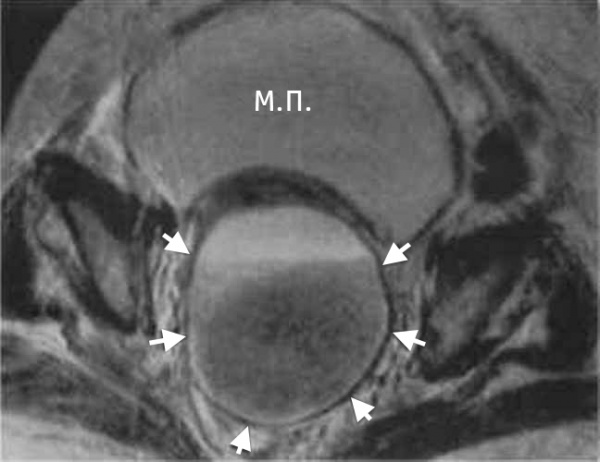

3. МРТ при тубоовариальном абсцессе:

• Т1-ВИ:

о Кистозное образование придатка с размытыми границами:

- Содержит жидкость, дающую сигнал низкой интенсивности

- Толстая стенка, имеющая неравномерную ширину

о Сигнал может быть гиперинтенсивным при наличии в содержимом продуктов распада крови или белка

о Вдоль внутренней стенки абсцесса может выявляться гиперинтенсивный ободок:

- Обусловлен образованием грануляционной ткани и кровоизлиянием

• Т2-ВИ:

о Кистозное образование придатков с размытыми границами и неоднородной структурой:

- Содержит жидкость, дающую сигнал от промежуточной до высокой интенсивности

- Неравномерная толщина стенки и перегородок, дающих гипоинтенсивный сигнал

о Отек жировой клетчатки параметрия, дающий гиперинтенсивный сигнал

о Гипоинтенсивные линейные фиброзные тяжи в тазовой жировой клетчатке

• Т1-ВИ с контрастированием:

о Усиление сигнала от кистозного образования придатков с перегородками и толстым ободком

о Сетчатый тяжистый рисунок тазовой жировой клетчатки:

- Соответствует спайкам и фиброзной ткани

4. УЗИ при тубоовариальном абсцессе: